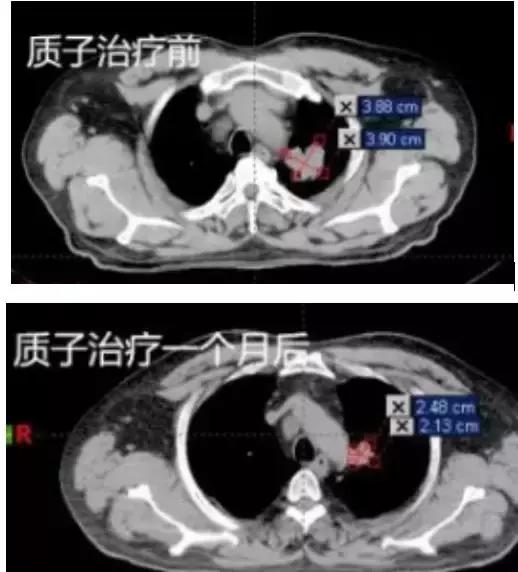

下面是一個(gè)晚期肺癌患者,經(jīng)質(zhì)子治療一個(gè)月后,腫瘤縮小65%的實(shí)例。

質(zhì)子治療一個(gè)月后,腫瘤明顯縮小。治療前大截面:3.88cm×3.90 cm,體積由44.56cm3;治療一個(gè)月后截面為2.48 cm×2.13 cm,體積15.68cm3;體積縮小65%。